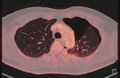

5. 2023/10/20 조영제 CT 촬영

2. 대표사진 - 사진 속 빨강 원이 문제의 결절

3. 사진을 동영상으로 변환. 노랑 원이 문제의 결절